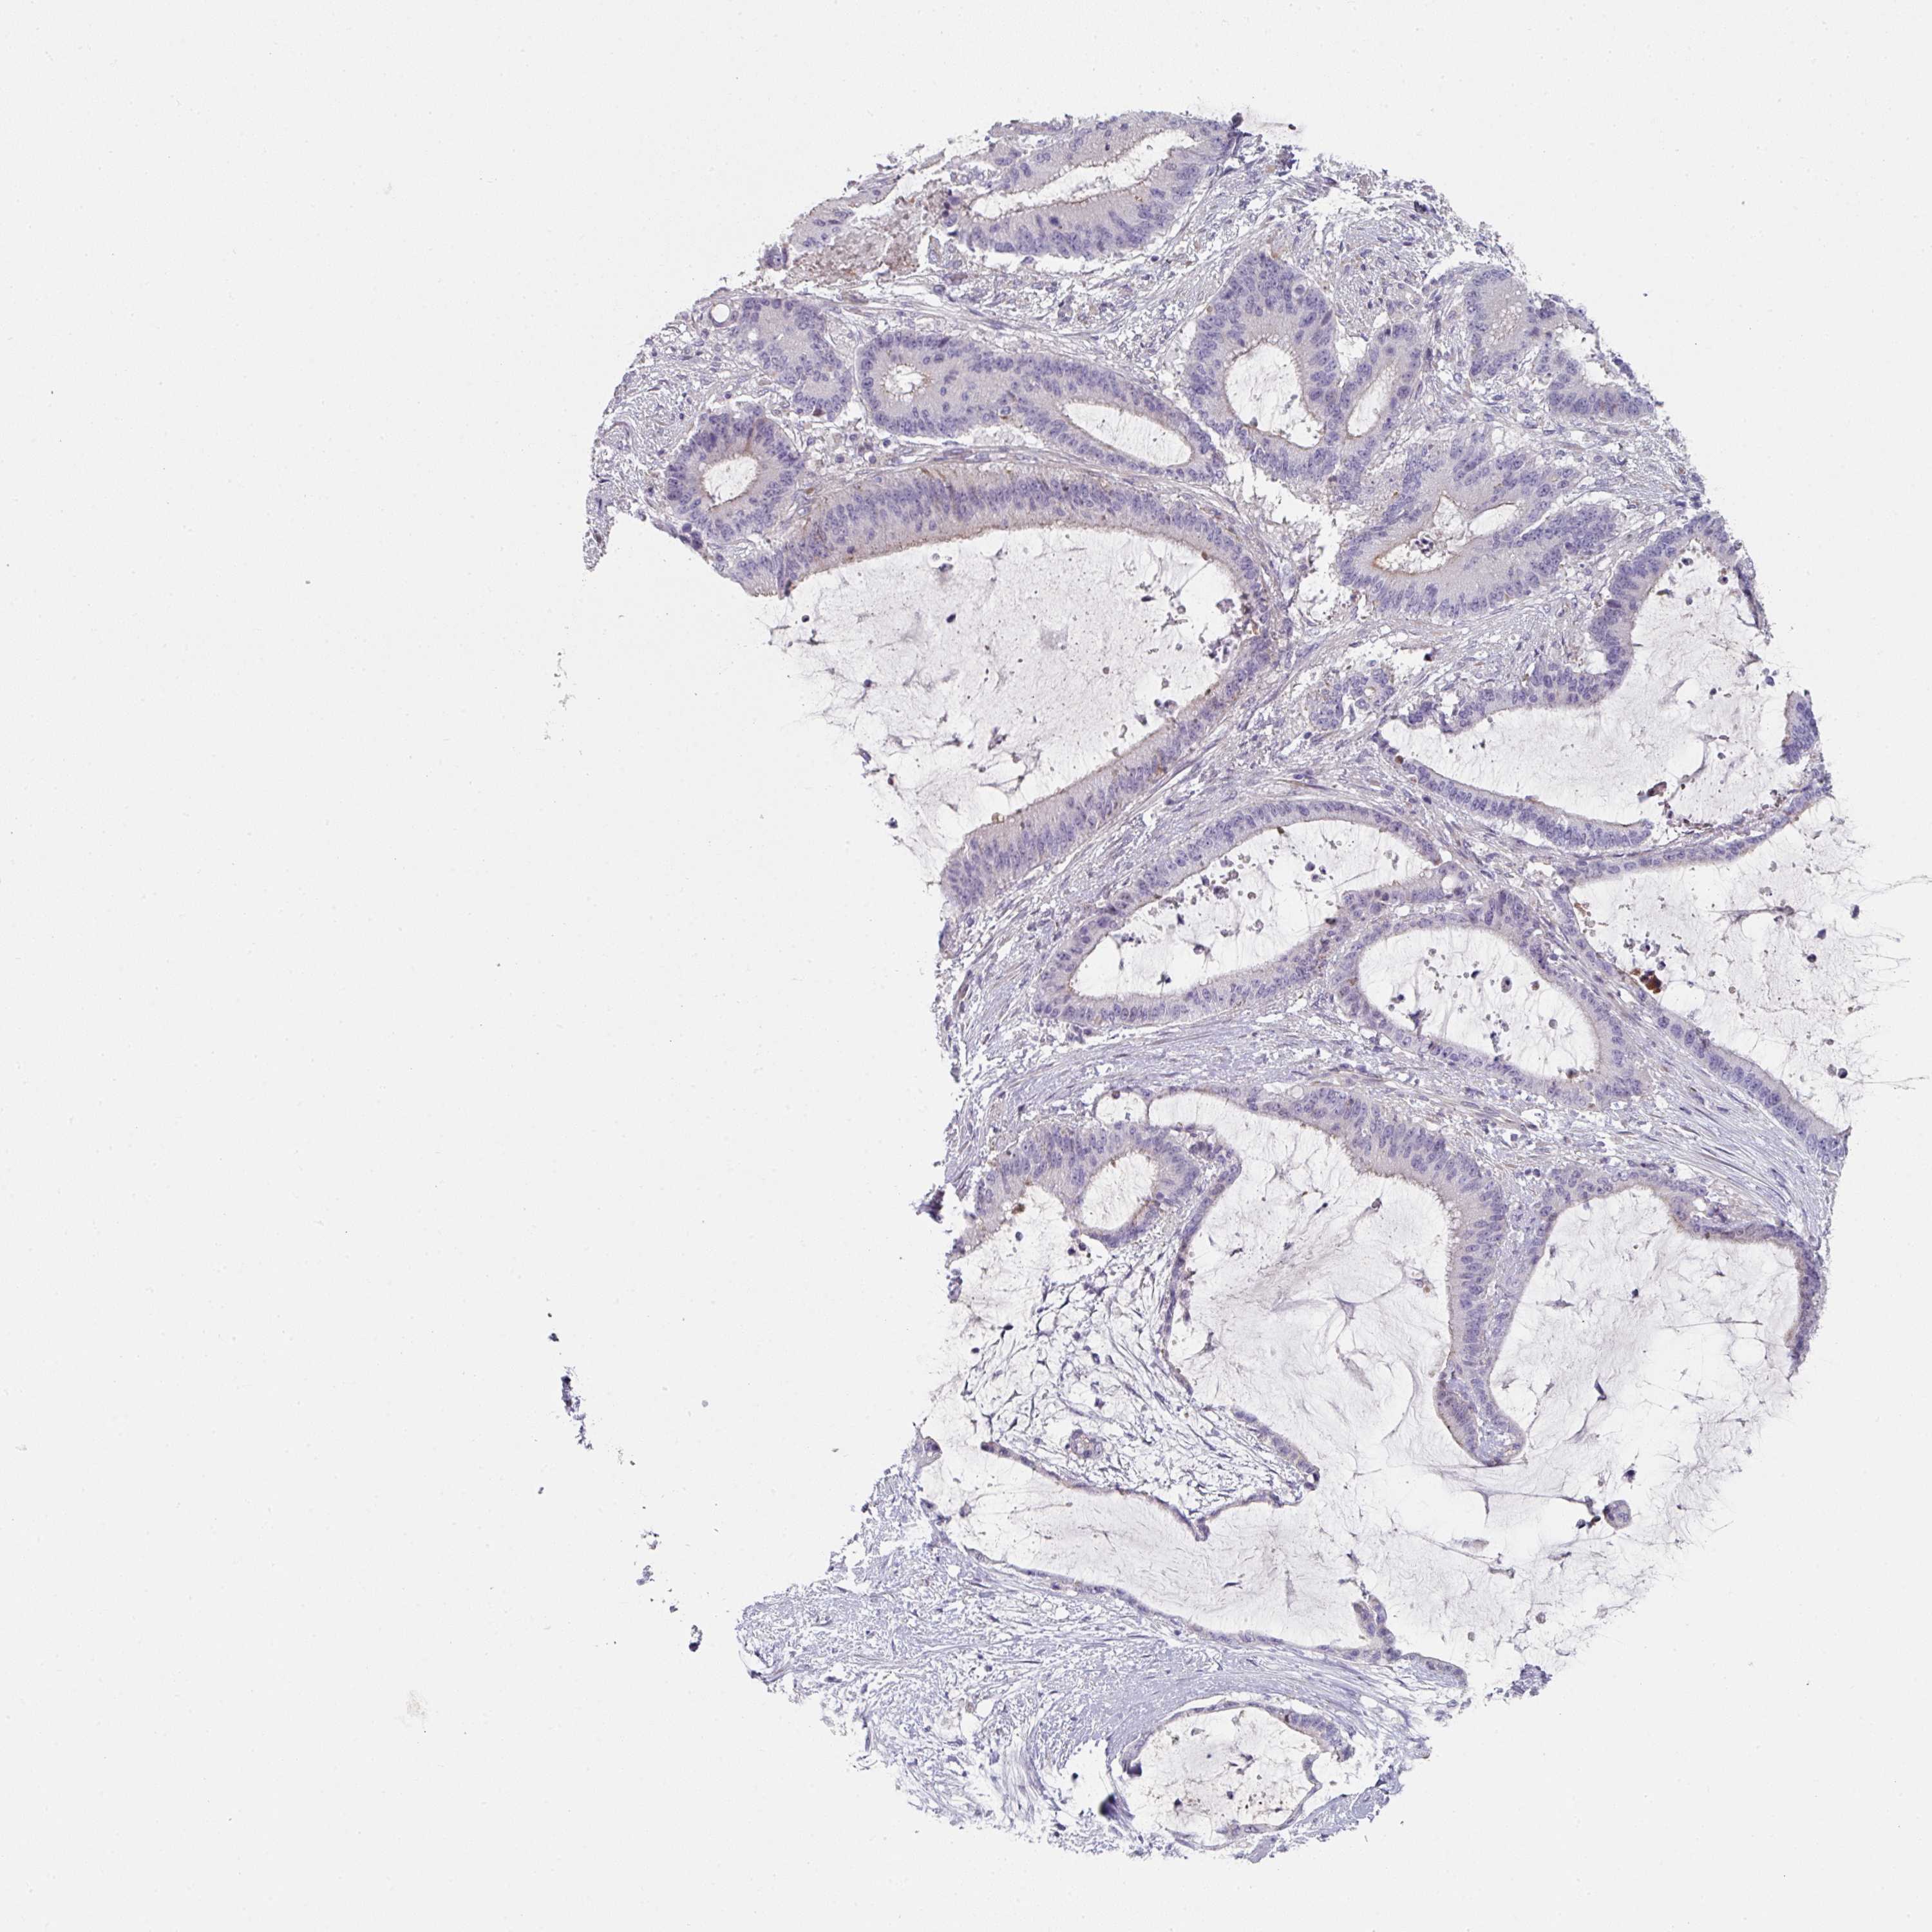

LIVER CANCER - Protein expressioni

A mouse-over function shows sample information and annotation data. Click on an image to view it in a full screen mode. Samples can be filtered based on level of antibody staining by selecting one or several of the following categories: high, medium, low and not detected. The assay and annotation is described here.

Note that samples used for immunohistochemistry by the Human Protein Atlas do not correspond to samples in the TCGA dataset.

Antibody stainingi

Antibody staining in the annotated cell types in the current human tissue is reported as not detected, low, medium, or high, based on conventional immunohistochemistry profiling in selected tissues. This score is based on the combination of the staining intensity and fraction of stained cells.

Each image is clickable and will lead to virtual microscopy that enables deeper exploration of all samples and also displays staining intensity scores, fraction scores and subcellular localization as well as patient and tissue information for each sample.

Antibody HPA052606

Antibody HPA077139

Staining

High

Medium

Low

Not detected

Intensity

Strong

Moderate

Weak

Negative

Quantity

>75%

75%-25%

<25%

None

Location

Nuclear

Cytoplasmic/membranous

Cytoplasmic/membranous,nuclear

Carcinoma, Hepatocellular, NOS

Cholangiocarcinoma